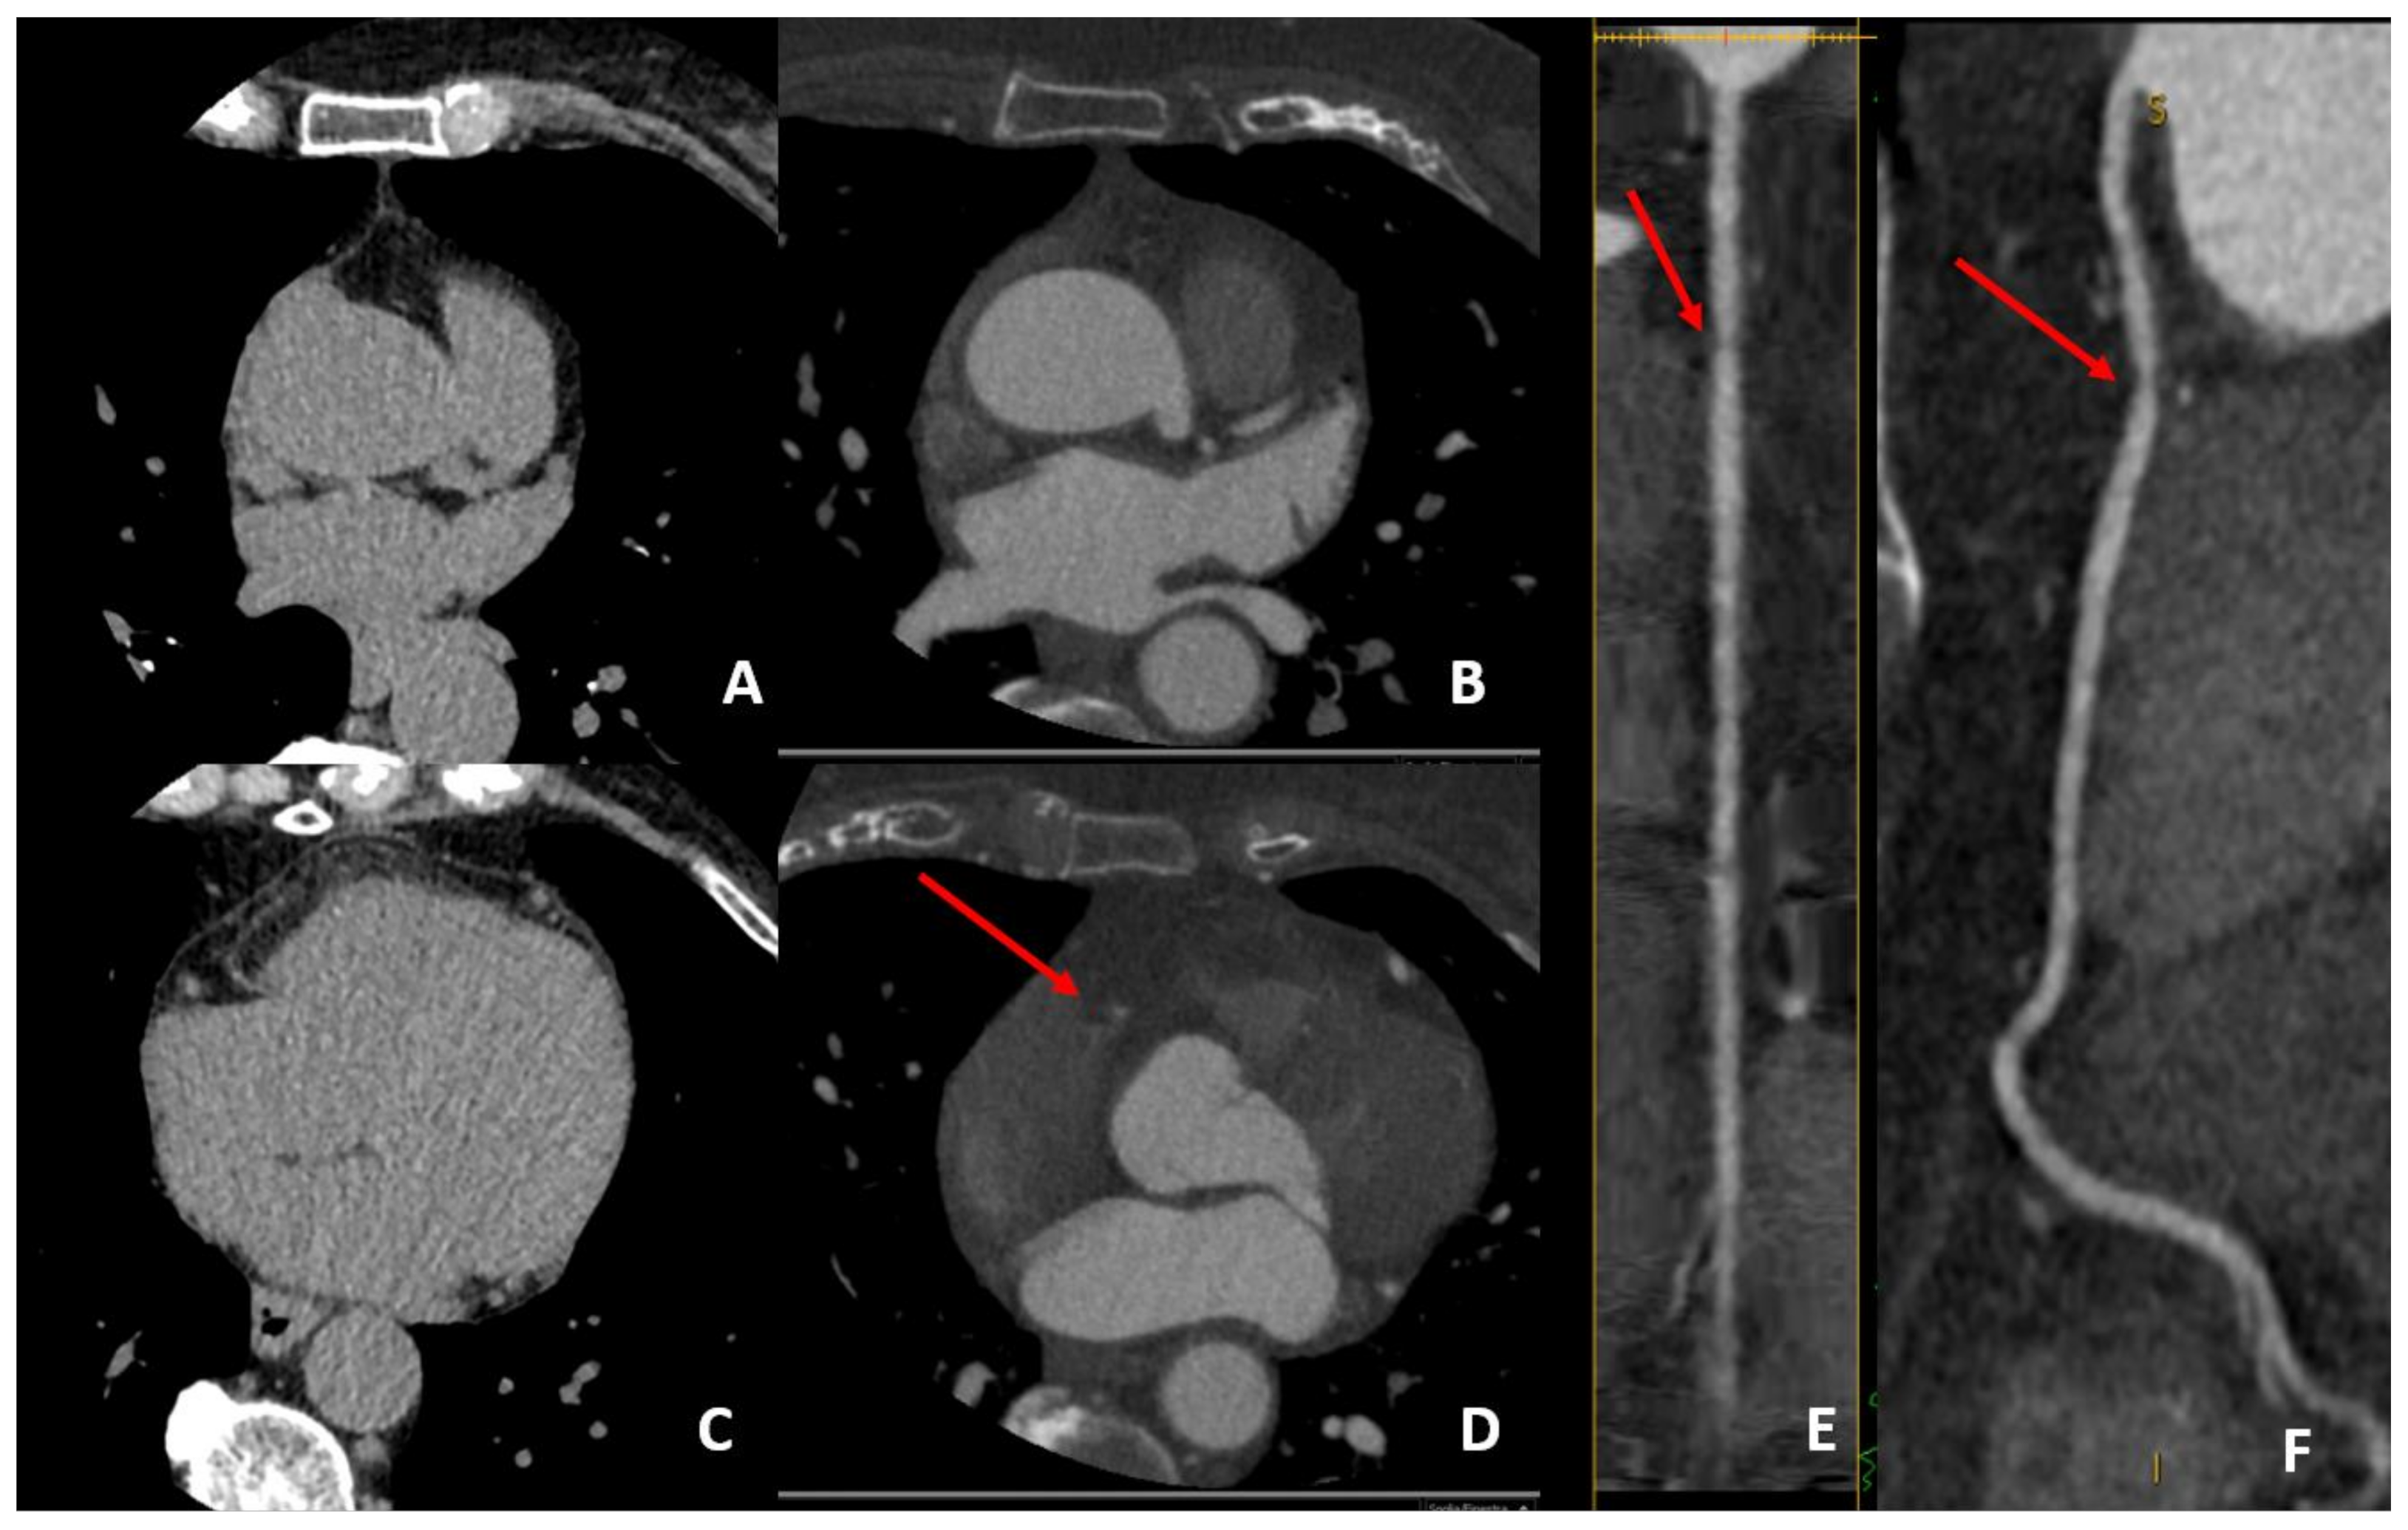

| Remodeling index (RI) | Ratio between lesion plaque area (red circle) and reference lumen area (blue circle). Positive remodeling is defined as RI > 1.1. | ![]() |

| Low-attenuation plaque (LAP) | Presence of any voxel < 30 HU in a coronary plaque. | ![]() |

| Plaque burden (PB) | Derived by the following formula: (lesion plaque area (red circle)—lesion lumen area (blue circle))/lesion plaque area (red circle). | ![]() |

| Napkin-ring sign (NRS) | Presence of rim-like thin enhancement (no more than 130 HU) distributed along the outer contour of the vessel and surrounding a fibro-lipidic plaque. | ![]() |

| Small spotty calcifications (SC) | Any discrete calcification ≤ 3 mm in length and occupying ≤ 90° arc when viewed on short axis. | ![]() |